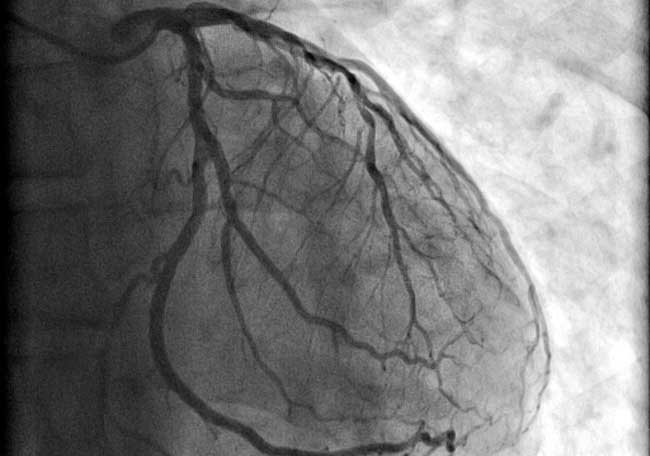

Los pacientes que buscan atención médica dentro de las 12 horas posteriores al inicio de los síntomas de un STEMI deben ser tratados con terapia de reperfusión. Esta terapia tiene como objetivo restaurar el flujo sanguíneo al área afectada del corazón lo más rápido posible. Existen dos enfoques principales para lograr esto: la angioplastia coronaria primaria, que implica el uso de un catéter para abrir la arteria bloqueada, y la terapia fibrinolítica, que utiliza medicamentos para disolver el coágulo que causa la obstrucción.

La diferencia en el enfoque terapéutico entre estos dos tipos de infarto se fundamenta en la fisiopatología subyacente y la naturaleza de la obstrucción coronaria. En el STEMI, el coágulo se forma rápidamente y la interrupción del flujo sanguíneo es aguda, mientras que en el infarto sin elevación del segmento ST, el proceso es más gradual y puede involucrar una combinación de factores isquémicos y mecánicos que no responden a la disolución del coágulo.